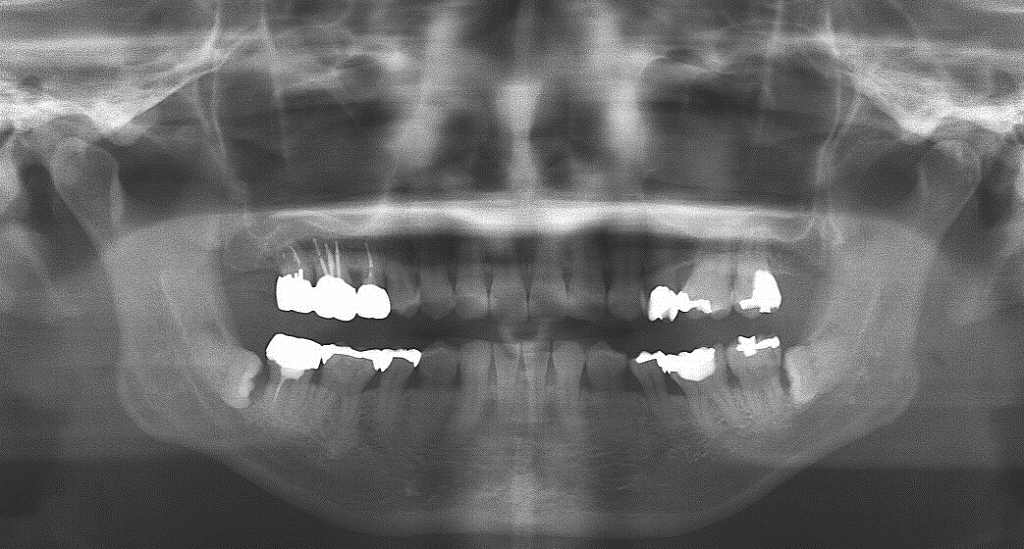

パノラマでは全体像がしっかりと見えています

40代後半の男性で歯間部にはしっかりと縁下歯石が付いていました

これをほっておくと手前の7番も歯周病が進んでグラグラしてきます